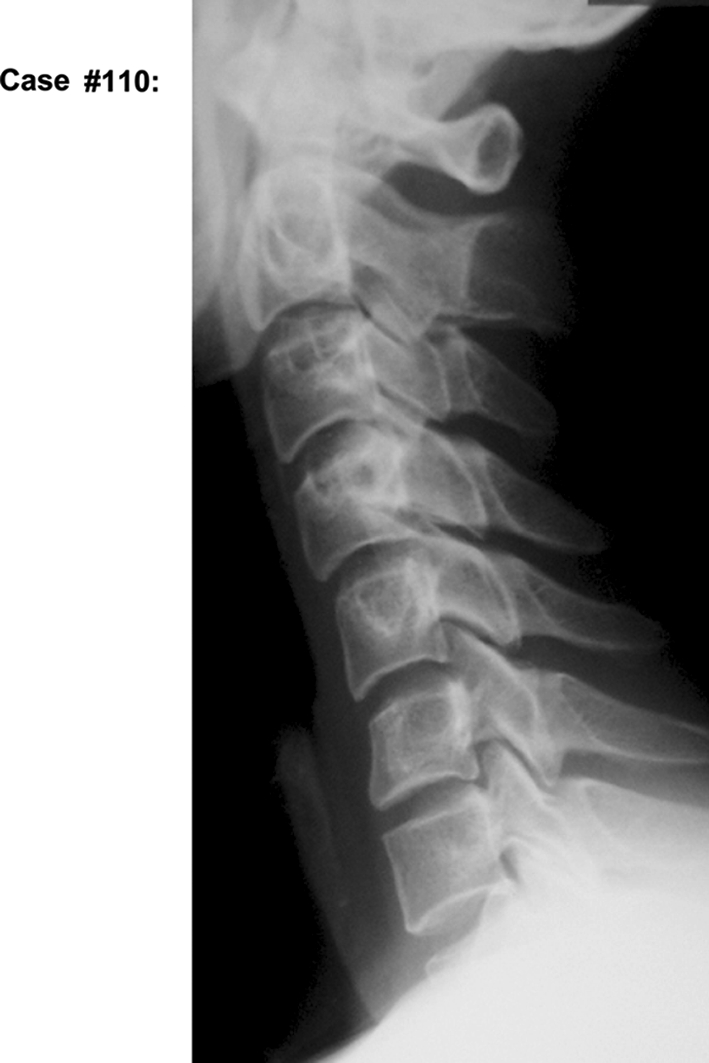

The sagittal alignment of the cervical spine was classified into two types, lordosis and non-lordosis type, the latter including straight sigmoid and kyphosis according to the classification reported by Chiba et al. [4] (Fig. 1). All participants were divided into four groups by their age (<40 years and ≥40 years) and the sagittal alignment (lordosis and non-lordosis) of the cervical spine: young lordosis (YL) group, n = 29; young non-lordosis (YNL) group, n = 36; old lordosis (OL) group, n = 34; and old non-lordosis (ONL) group, n = 14. The cut-off line of the age at 40 years was chosen according to the study reported by Boden et al. [1] regarding aging in the cervical intervertebral disks. The items evaluated on MRI were (1) decrease in signal intensity of disk, (2) posterior disk protrusion, and (3) disk space narrowing. Each item was evaluated using the Matsumoto’s [22] classification with a minor modification, which was used in our previous report (Table 2).

Fig. 1.

Sagittal alignment of cervical spine. A line is drawn between the lower posterior corner of the C2 and C7, and this line is defined as “A.” Perpendicular lines are drawn from the lower posterior edge of the bodies of C3–C6 to this line, and the length of these lines is defined as a1–a4. If every a1–a4 is anterior to “A” and one of them is more than 2 mm, the curvature is defined as lordosis. If every a1–a4 is posterior to “A” and one of them is more than 2 mm, the curvature is defined as kyphosis. If every a1–a4 is less than 2 mm, the curvature is defined as straight. If a1–a4 exists both anterior and posterior and one of them is more than 2 mm, the curvature is defined as sigmoid